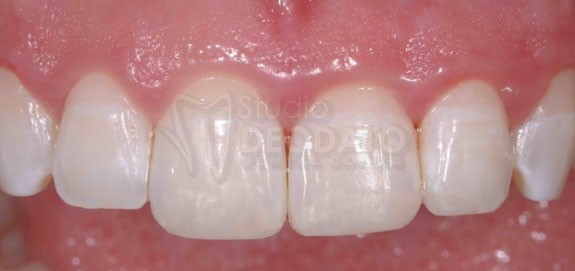

Esempio clinico di restauro diretto od otturazione in composito

Frattura dell’incisivo centrale e laterale risolti per mezzo di due restauri diretti in composito.